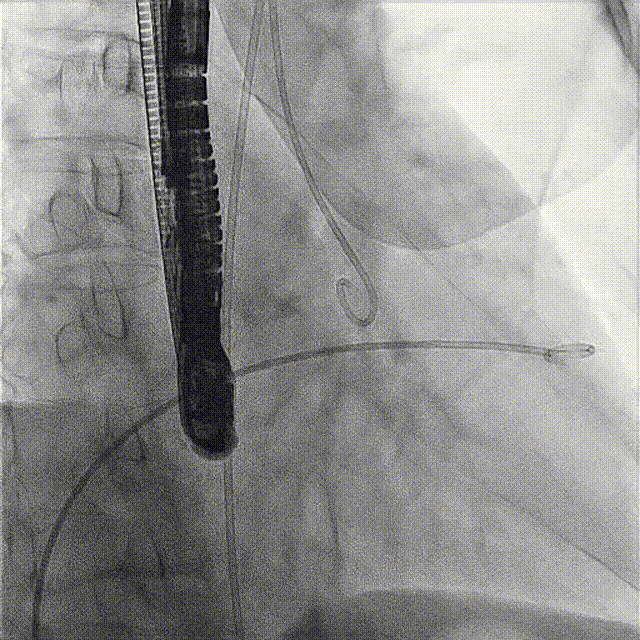

術前DSA

術前經(jīng)過全面系統(tǒng)的評估后,考慮患者存在高齡、心功能減低、三尖瓣瓣環(huán)重度擴張(三尖瓣極重度反流)等高危因素,因此廈心結構心團隊聯(lián)合超聲心動、麻醉及護理團隊,制定了詳盡的圍術期治療方案及術中治療難點預案。術中,由王焱院長主刀,在蘇茂龍主任超聲心動團隊的輔助,上海市第一人民醫(yī)院陸方林主任的協(xié)助下,僅用時30分鐘,即順利完成了三尖瓣原位置換的手術。術中患者血流動力學穩(wěn)定,術后即刻顯示LuX-Valve Plus瓣膜位置良好,固定穩(wěn)定,瓣膜功能正常,無瓣周漏。